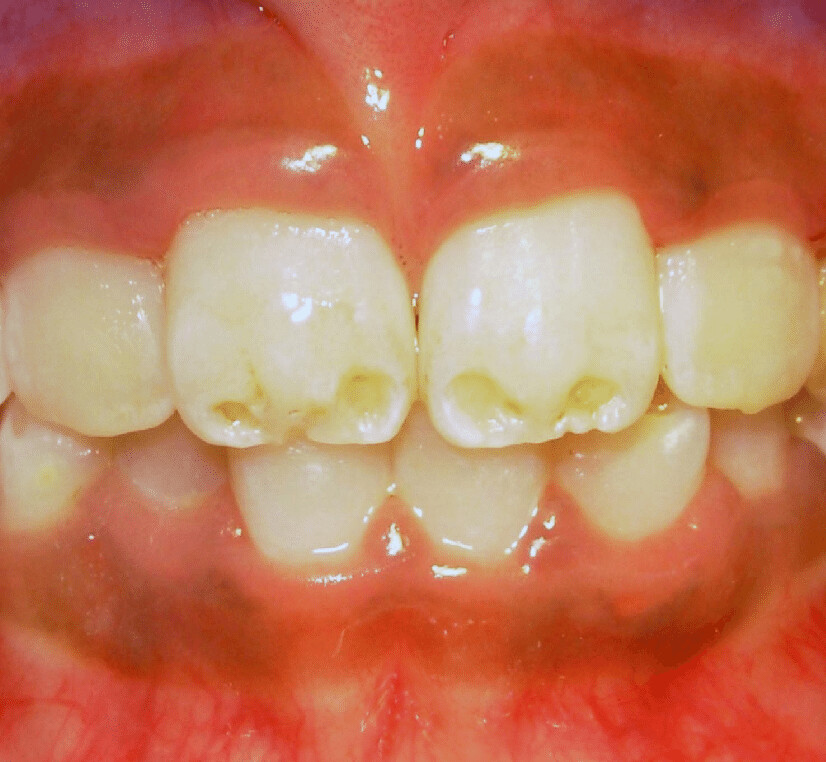

On the other hand, enamel hypoplasia is a condition where teeth have pits, grooves, and missing enamel. It can also result in smaller teeth. Hypoplasia appears as brown or yellow stains and exposed dentin. While the enamel is still hard, it is weak. This is a type of amelogenesis imperfecta, where the enamel on teeth is missing or severely thin and prone to breaking.

There are several causes as to how and why these conditions form. According to the Indian Journal of Dentistry, these conditions occur when there is a disturbance in the matrix formation of the teeth. To break that down, let’s look at ameloblasts, which are your teeth’s enamel-producing cells. These cells form in six stages: morphogenetic, organising, formative, maturative, protective, and desmolytic. Enamel hypoplasia happens in the formation stage, resulting in the pitting, grooving, or even total absence of enamel. Hypomineralisation happens in the maturative stage and can appear as “chalky” areas on your tooth’s enamel.